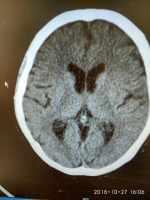

腦梗死致病頭部不適伴高血壓病一例 關鍵疾?。?a href="http://m.akellydesign.com/tags/so/腦梗死-4-1.html" target="_blank">腦梗死高血壓病 現(xiàn)病史【一般資料】 女性,75歲,農民 【主訴】女性,75歲,農民頭部不適7天入院。 【現(xiàn)病史】入院前7天,無明顯誘因下出現(xiàn)頭部不適,呈持續(xù)性;無惡心,無嘔吐,無意識障礙及大小便失禁,無流涎,飲食無嗆咳,無咳嗽、咴痰,無腹痛、腹瀉。為求診治,來我院就診,頭顱CT:兩側基底節(jié)區(qū)多發(fā)腔梗。以“腦梗死”收入院。自發(fā)病來,精神正常,食欲尚可,睡眠及二便如常。 【既往史】既往高血壓病史12年,最高220/110mmHg,規(guī)律口服尼群地平血壓控制尚可;無肝炎、結核及其他傳染病史;無外傷及輸血史;無藥物及其他過...